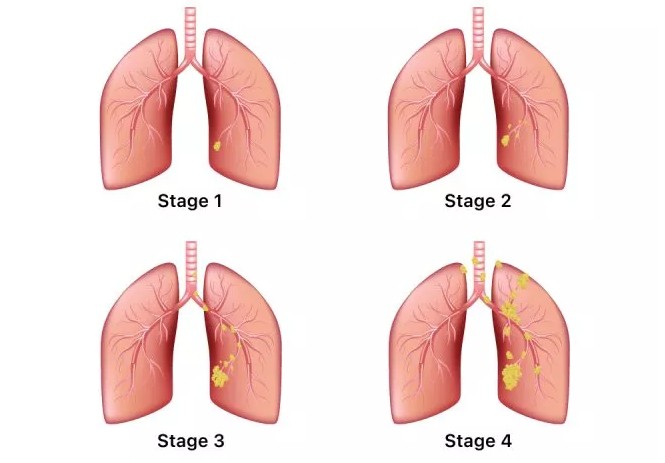

폐암은 위암, 갑상선암 다음으로 3번째로 발병 빈도가 높은 3대 암 중 한 가지입니다. 폐암은 재발과 전이까지의 빈도도 잦은지라 완치가 어렵다고 하며 폐암 발병 초기에는 거의 증상이 없을 수가 있어 수술이 불가능한 3기, 혹은 4기에 주로 진단된다고 합니다.

폐암 4기에 이르게 되면 5년 생존률이 30% 대로 떨어지게 된다고 합니다. 그리해서 폐암은 암 질병이자 중 사망자 비율이 가장 높은 것으로 나타나고 있습니다.